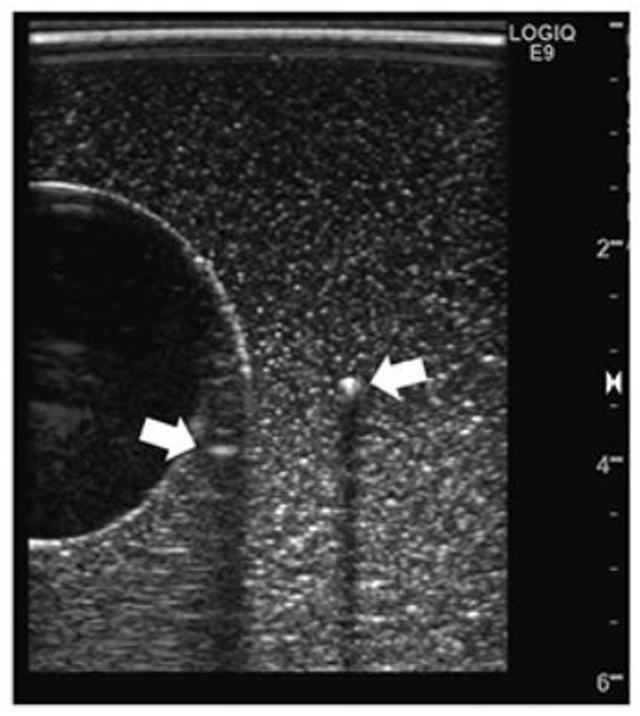

若 杉:圧排性増殖に関連する事項として,HCCの外側陰影について説明します(図3).

▲本実験のBモード像.右の矢印:金属棒(強反射体),左の矢印:その鏡面反射.

▲走査線の屈折現象のシミュレーション結果.左図:走査線の経路,右図:臨界角による全反射のモデルを付加すると,実験と対応するBモード像が得られた.

図3 外側陰影の形成(文献1より引用)

若 杉:外側陰影(lateral shadow)の形成機序については,これまでは屈折だけで説明されていました.多くの教科書でも屈折で説明されています.しかし屈折だけだと陰影には見えず,画像の歪みとして見えるはずなんですよね.近年は,超音波ビーム(送信波)と線維性被膜の角度が臨界角以上であるとビームが全反射し,この際の被膜壁形状が凸なため音波の散乱減衰が生じてしまい,外側陰影ができるといわれています.すなわち,腫瘍境界部での散乱減衰が外側陰影をもたらすのではないかといわれています.